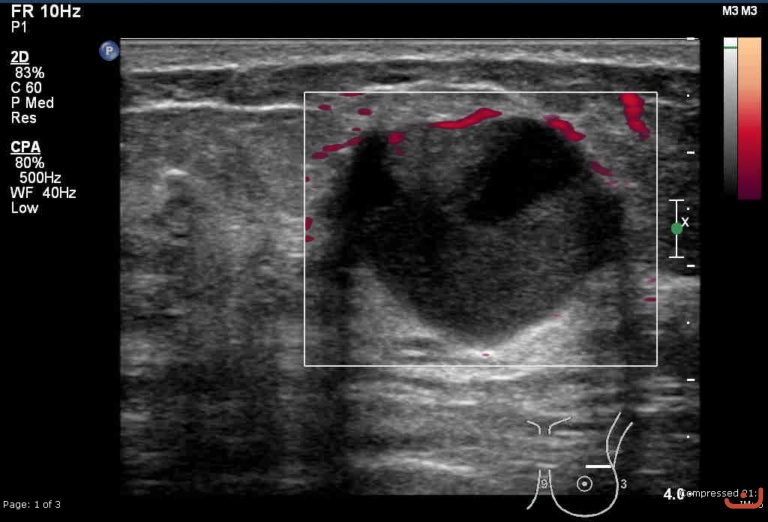

Malignant solid mass

Friday, 22 May 2015